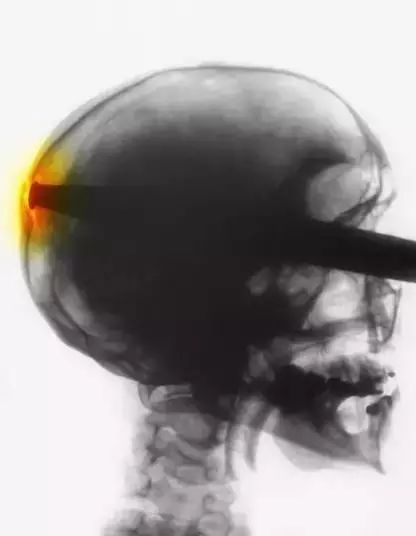

7、这名不幸的患者被一根撬棍刺穿头部。